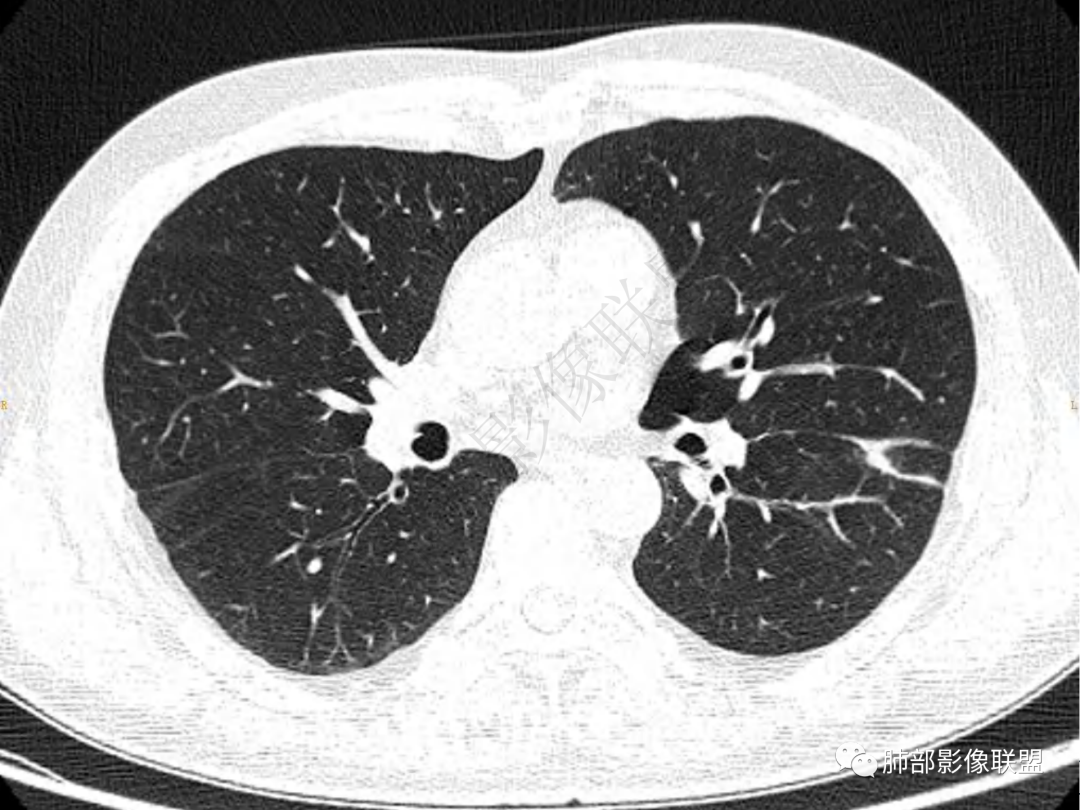

1.中年男性,咳嗽咳痰20余天,间断咯血2周

2.左肺下叶团片影,跨背段及内前基底段,实性部分类椭圆形,密度不甚均匀,可见毛刺及棘状突起,未见典型分叶及胸膜凹陷。病灶上下缘可见相应肺段支气管旁进侧出,管壁轻度增厚,未见狭窄阻塞。

3.周边较大范围磨玻璃影,边界相当模糊,小叶增厚明显。注意叶裂另一侧、左肺舌段亦可见磨玻璃影及增厚的小叶间隔。未见明确卫星病灶。

4.实性部分不均匀环形强化并显示一小范围低密度坏死区或空洞。较之肺窗,整体纵隔窗范围较小,提示病灶并不十分密实。抑或为不同时段图像。

5.双肺门及纵隔未见增大淋巴结。未见胸腔积液。